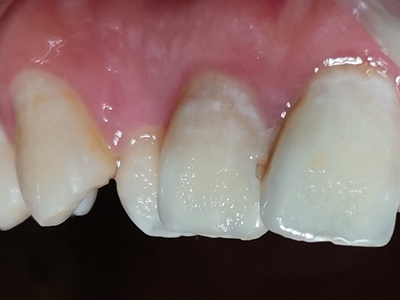

牙龈炎是发生于牙龈组织的炎症,患者可出现牙龈出血伴肿胀、发红、正常形态改变和偶尔不适等症状。本病主要由口腔卫生状况差导致,包括口腔不洁、牙菌斑等,诊断依据临床检查,治疗包括专业牙齿清洁和加强家庭口腔卫生。

牙龈炎可先引起牙齿与牙龈之间的沟(龈沟)加深,然后牙龈充血,炎症围绕一个或多个牙齿,伴牙龈乳头肿胀和易出血。一般无痛,可自行消退,也可维持轻度炎症数年。

牙龈炎常见的病因是口腔卫生差,不良的口腔卫生使牙菌斑沉积于牙齿与牙龈之间,造成龈沟加深,另外牙结石、不良修复体等也可造成牙龈炎的发生。